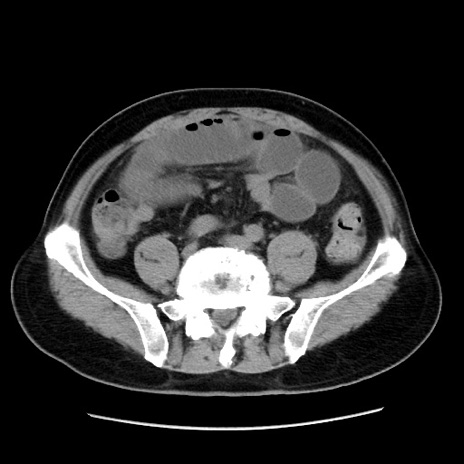

症例16(横断像)

【症例】 70歳代男性

【主訴】 腹痛、嘔吐

【現病歴】 約1ヶ月前より間欠的に腹痛と嘔吐あり、当院消化器内科を受診したところCTで多発する肝臓のLDAを指摘され、精査中であった。以降は消化器症状は安定していたが、2日前より嘔気と腹痛があり、同日より排便・排ガスが消失した。改善認めず、 本日、救急外来を受診した。

【既往歴】 大腸ポリープ切除後。

【身体所見】意識清明・会話良好、BT 36.3℃、BP 127/80mmHg、 P 80bpm、腹部:膨満あり、平坦・軟、上腹部正中および下腹部正中に圧痛あり、反跳痛なし、筋性防御なし。

【データ】WBC 7200、CRP 0.77